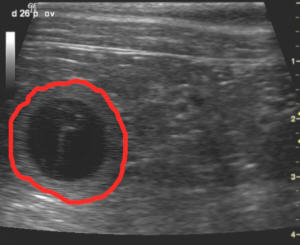

Hier ein paar von den Ultraschallbildern. Die mit rot umrandete Fläche ist ein h in seiner Hülle.